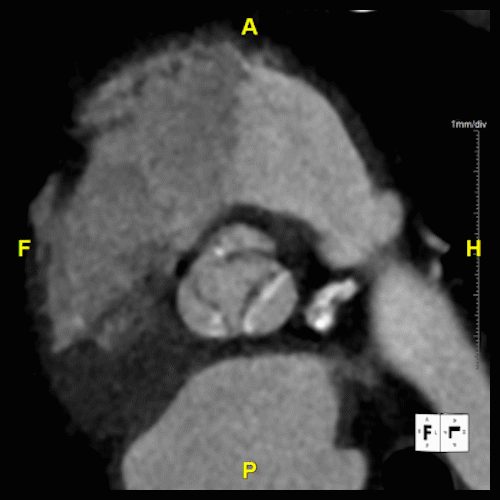

Our service for Transcatheter Aortic Valve Replacement (TAVR) utilizes 3D imaging and measurements to enhance procedural planning. These images may be useful for mapping the intricate landscape of cardiac structures and vasculature, ensuring each transcatheter heart valve (THV) procedure is customized to the patient's unique anatomy.

Using 3D imaging in the TAVR planning process allows for the evaluation of aortic root dimensions, annulus size, and the morphology of the aortic valve complex. It provides insights into the spatial relationships between the aortic valve and surrounding coronary arteries, highlighting potential challenges and guiding the selection of the appropriate valve size and optimal implantation approach.

Additionally, CT angiography assesses the iliofemoral arteries, determining their suitability for catheter access by identifying any calcifications, occlusions, or tortuosities that could impact the procedure.